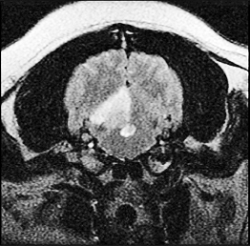

Ischemic stroke (or cerebellar ischemic stroke) is a sudden blockage of the blood flow to an area of the cerebellum of the brain caused either by a blood clot.* The blockage deprives the delivery of oxygen to that portion of the brain, creating a dead tissue lesion, typically wedge-shaped (see MRI image at right), called a cerebellar infarct. This usually results in the loss of some neurological function which had been controlled by the affected area of the brain.

The only accurate way to diagnose an infarction is using magnetic resonance

imagine (MRI), and to a limited extent, computed tomography (CT), to obtain

scans of brain images. Early enough CT imaging should enable the veterinarian to

determine whether the infarct was caused by a burst blood vessel (hemorrhagic),

but MRI is the best device for identifying a shut down blood vessel (ischemic),

which will better determine the treatment protocol.

... Cerebellar infarction appears to have characteristic MRI features. Affected tissue within the cerebellum is typically wedge-shaped with low signal intensity in T1-weighted images, high signal intensity in T2-weighted images, subtle rim enhancement without central contrast enhancement in T1 post-gadolinium, and selectively hyperintense in fluid-attenuated inversion recovery images. Anatomic regions serviced by rostral cerebellar arteries are affected. Vascular risk factors as compared with reports in human literature are also discussed."